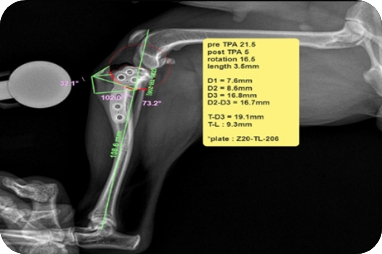

전방십자인대 파열(TPLO)

수술(TPLO)